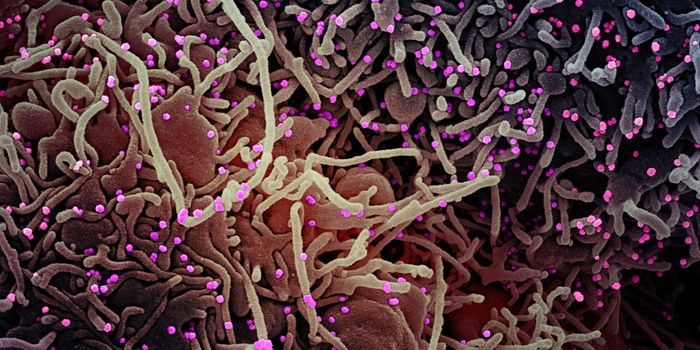

JUL 11, 2021MicrobiologyIn October 2020, what's now called the Delta variant of SARS-CoV-2 was first detected. It's now the most prevalent strai ...